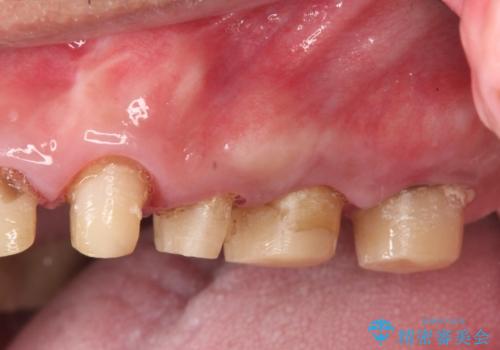

虫歯だらけの歯を治療したい

- 「虫歯が多発し、治療が終わらない。歯も無くなったし今後悪くならないような治療をしたい。」と精密治療を希望され来院されました。

虫歯の徹底的な除去やセラミック補綴、精密根管治療、歯周外科を行うことで、治療後に歯磨きがしやすく、かみやすい機能的な仕上がりへと導きます。